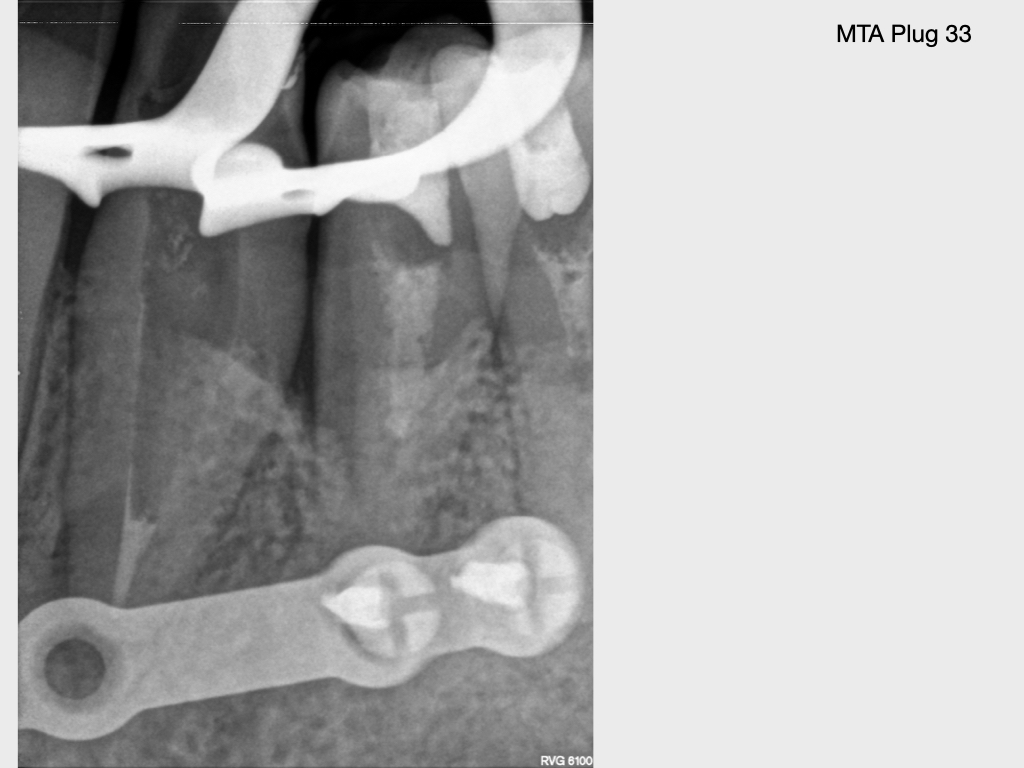

Submuköser Abszess 33 (3)